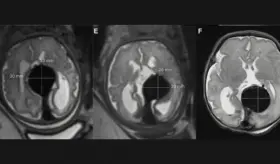

El Dr. Ricardo Santiago fue el primer puertorriqueño y latinoamericano invitado como operador en vivo en este evento internacional. Especialista en oclusiones totales crónicas (CTO) y procedimientos coronarios de alto riesgo, transmitió dos casos complejos en tiempo real.